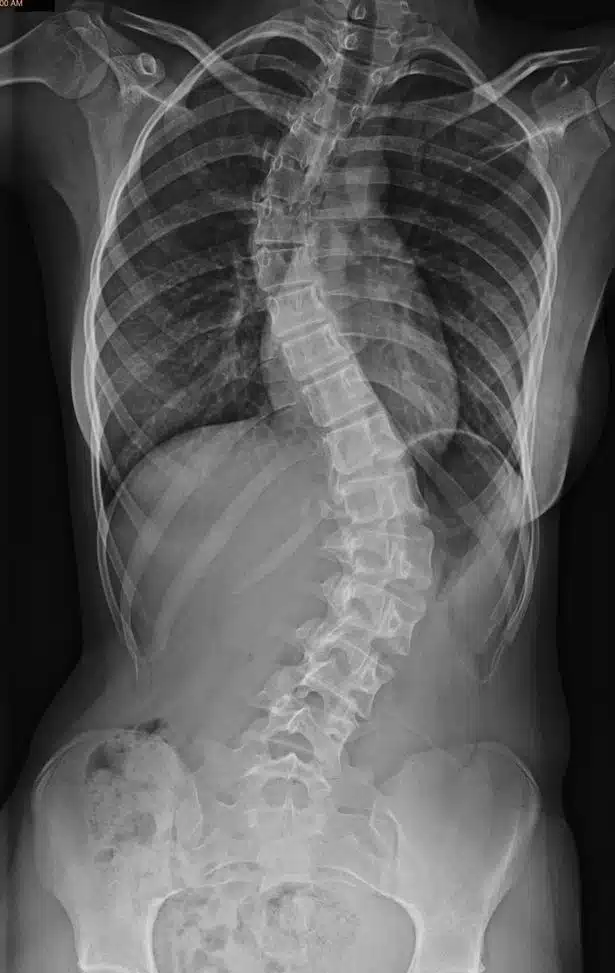

To identify spinal stenosis, your physician may request you about signs and symptoms and then performs a physical examination. He may perform several imaging tests to determine the cause of your signs and symptoms. Imaging tests may include X-Ray or MRI. Your X-ray or MRI can show bone changes, such as spur bones, which may narrow the space in the spinal canal and the doctor prescribes you spinal canal stenosis surgery.

Most people with spinal stenosis are over 50 years of age. Although corrosive variations can cause spinal cord injury in humans, other factors must also be considered. These include congenital disorders and disorders such as scoliosis and genetic disease that affect bone and muscle growth in the body. Spine imaging can distinguish these causes.